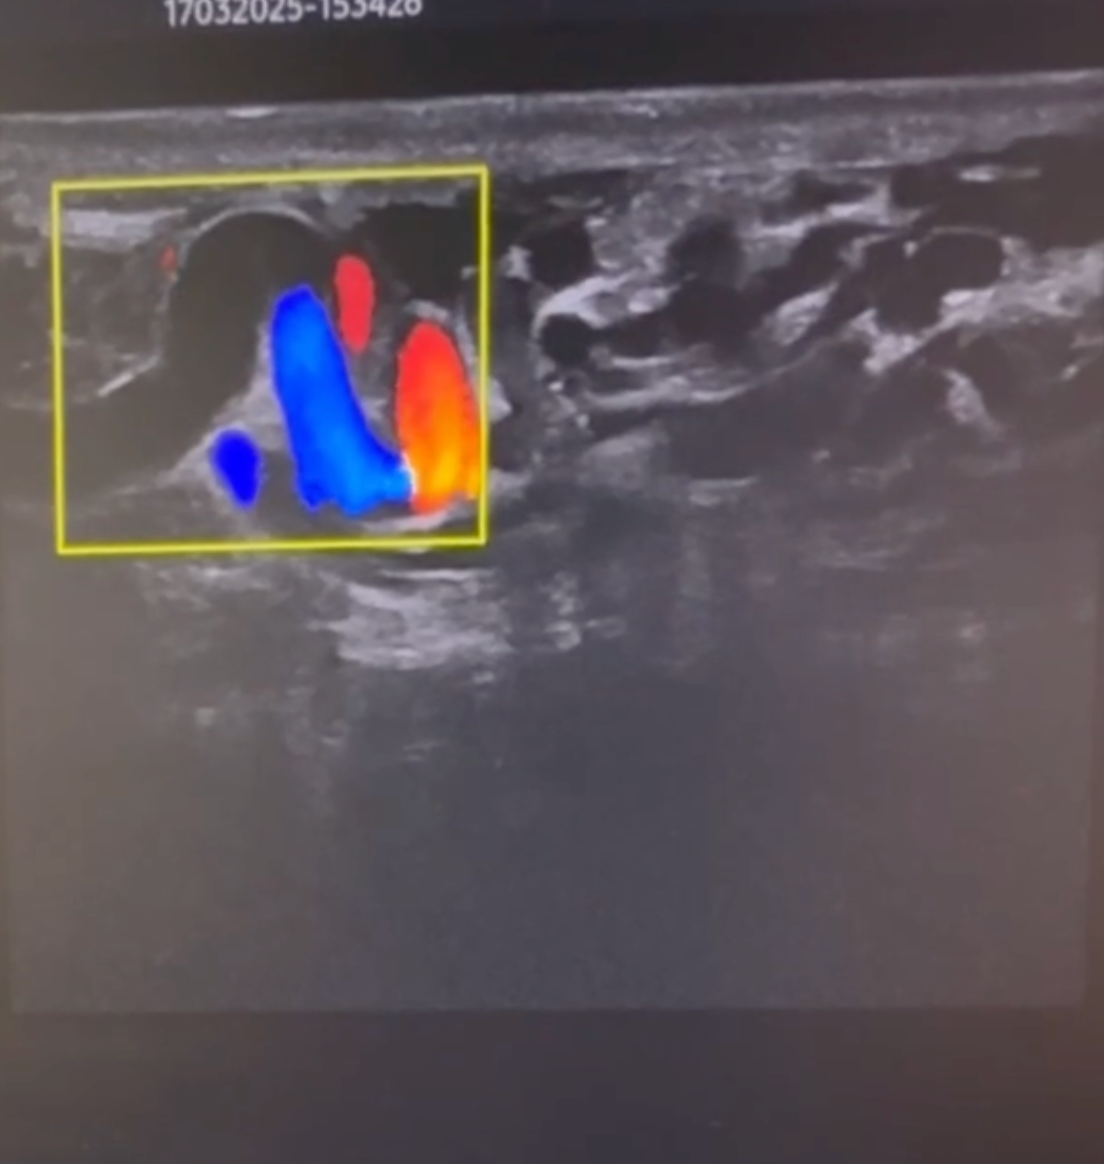

УЗИ органов мошонки